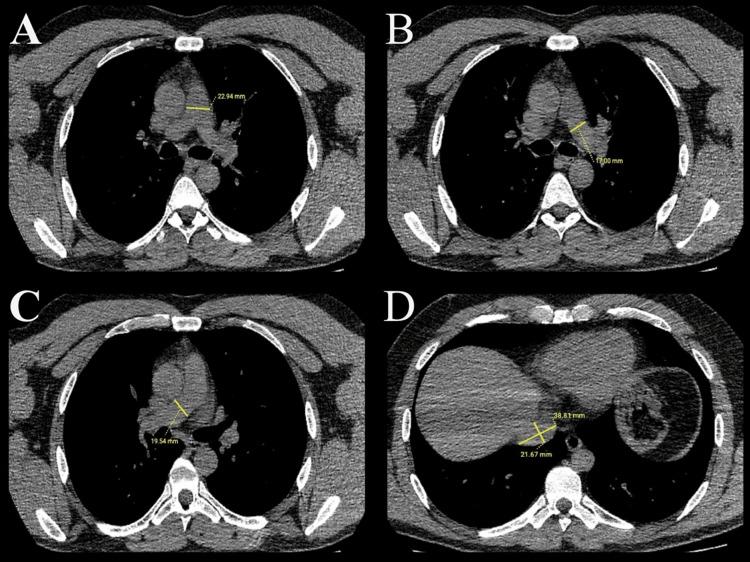

Background The COVID-19 infection has spread rapidly since its emergence and has affected a large part of the global population. With the increasing number of cases, researchers are trying to predict the prognosis of patients by using different data with artificial intelligence methods such as machine learning (ML). In this study, we aimed to predict mortality risk in COVID-19 patients using ML algorithms with different datasets. Methodology In this retrospective study, we evaluated the fever, oxygen saturation, laboratory results, thorax computed tomography (CT) findings, and comorbid diseases at admission to the hospital of 404 patients whose diagnosis was confirmed by the reverse transcription polymerase chain reaction test. Different datasets were created by combining the data. The Synthetic Minority Oversampling Technique was used to reduce the imbalance in the dataset. K-nearest neighbors, support vector machine, stochastic gradient descent, random forest, neural network, naive Bayes, logistic regression, gradient boosting, XGBoost, and AdaBoost models were used to create the ML algorithm, and the accuracy rates of mortality prediction were compared. Results When the dataset was created with CT parenchyma score, pulmonary artery and inferior vena cava diameters, and laboratory results, mortality was predicted with an accuracy of 98.4% with the gradient boosting model. Conclusions The study demonstrates that patient prognosis can be accurately predicted using simple measurements from thorax CT scans and laboratory findings.

背景 自新冠病毒病(COVID-19)感染出现以来迅速传播,已影响全球大部分人口。随着病例数增加,研究人员正尝试通过机器学习(ML)等人工智能方法利用不同数据预测患者预后。在本研究中,我们旨在使用不同数据集的ML算法预测COVID-19患者的死亡风险。方法 在这项回顾性研究中,我们评估了404例经逆转录聚合酶链反应检测确诊的患者入院时的发热、血氧饱和度、实验室检查结果、胸部计算机断层扫描(CT)结果及合并症。通过合并数据创建不同数据集。使用合成少数过采样技术减少数据集中的不平衡。使用K近邻、支持向量机、随机梯度下降、随机森林、神经网络、朴素贝叶斯、逻辑回归、梯度提升、XGBoost和AdaBoost模型创建ML算法,并比较死亡预测的准确率。结果 当使用CT实质评分、肺动脉和下腔静脉直径及实验室检查结果创建数据集时,梯度提升模型预测死亡率的准确率为98.4%。结论 该研究表明,使用胸部CT扫描的简单测量结果和实验室检查结果可准确预测患者预后。